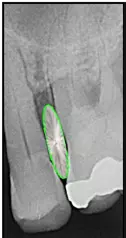

Dabei umfassen die ISO-Gruppengrößen 1 bis 3 jeweils zwei PHD-Werte, die Größen 4 bis 5 drei und die Größen 6 bis 7 fünf PHD-Werte. Alle Bürsten mit einem PHD von > 2,9 erhalten die ISO-Größe 8. Obwohl die neue Norm ein großer Fortschritt ist, führen die heterogenen ISO-Gruppengrößen vor allem bei größeren Interdentalraumbürsten zu ungenügender Differenzierung. Nicht alle Bürsten der gleichen ISO-Gruppengröße können denselben Interdentalraum passieren (Abb. 3). Entscheidend ist daher die Orientierung am einzelnen PHD-Wert und nicht an der ISO-Gruppengröße [28].

Man benötigt gerade in solchen Situationen ein ausreichendes Sortiment größerer Interdentalraumbürsten, wenn man das Ziel verfolgt, bei der Anwendung den jeweiligen Taschenfundus zuverlässig zu erreichen (Abb. 5).